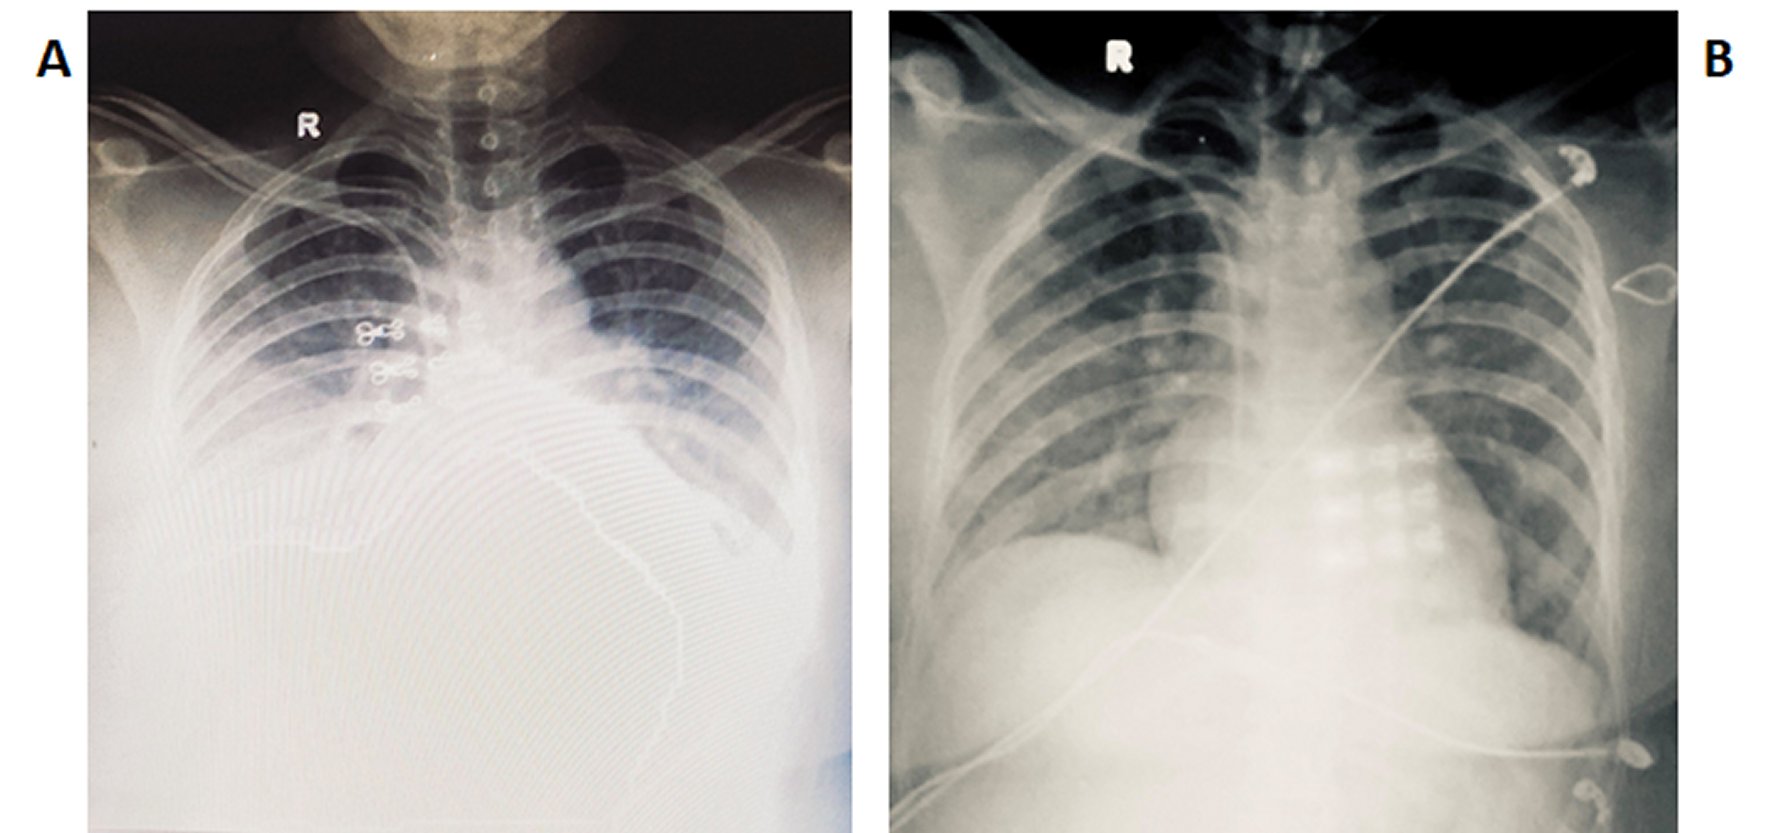

On day 3 of admission, she developed shortness of breath and oxygen saturation started falling. She was hooked with an oxygen mask at oxygen at 8L/min. Immediate chest X-ray showed left lower zone consolidation (Figure 1A) for which antibiotic and steroid were added. Piperacillin/Tazobactem at 4.5g every 8hourly was continued for 7 days. 200mg of intavenous hydrocortisone was given stat and then 100mg every 8 hourly was continued for 7days. She required oxygen for the next 36 hours and we were able to gradually taper off the oxygen requirement. She was completely stable on day 4 of admission to the ICU and magnesium sulfate infusion was continued for 5 days.

She was shifted to the medical ward on 6th day. Oral feeding with sips and liquid diet was started on the same day, which was gradually progressed to solid diet. Psychiatric consultation was done on the same day. She tolerated well to the liquid and solid diets and improved symptomatically. Repeat routine investigations were carried out on the 8th day, which was within normal limit. The Chest X-ray showed resolved consolidation (Figure 1B). The patient was discharged on 8th day and advised for follow-up in 7 days. Her follow-up visits were carried out at regular intervals for 1-month along with psychiatric evaluation on each visit.